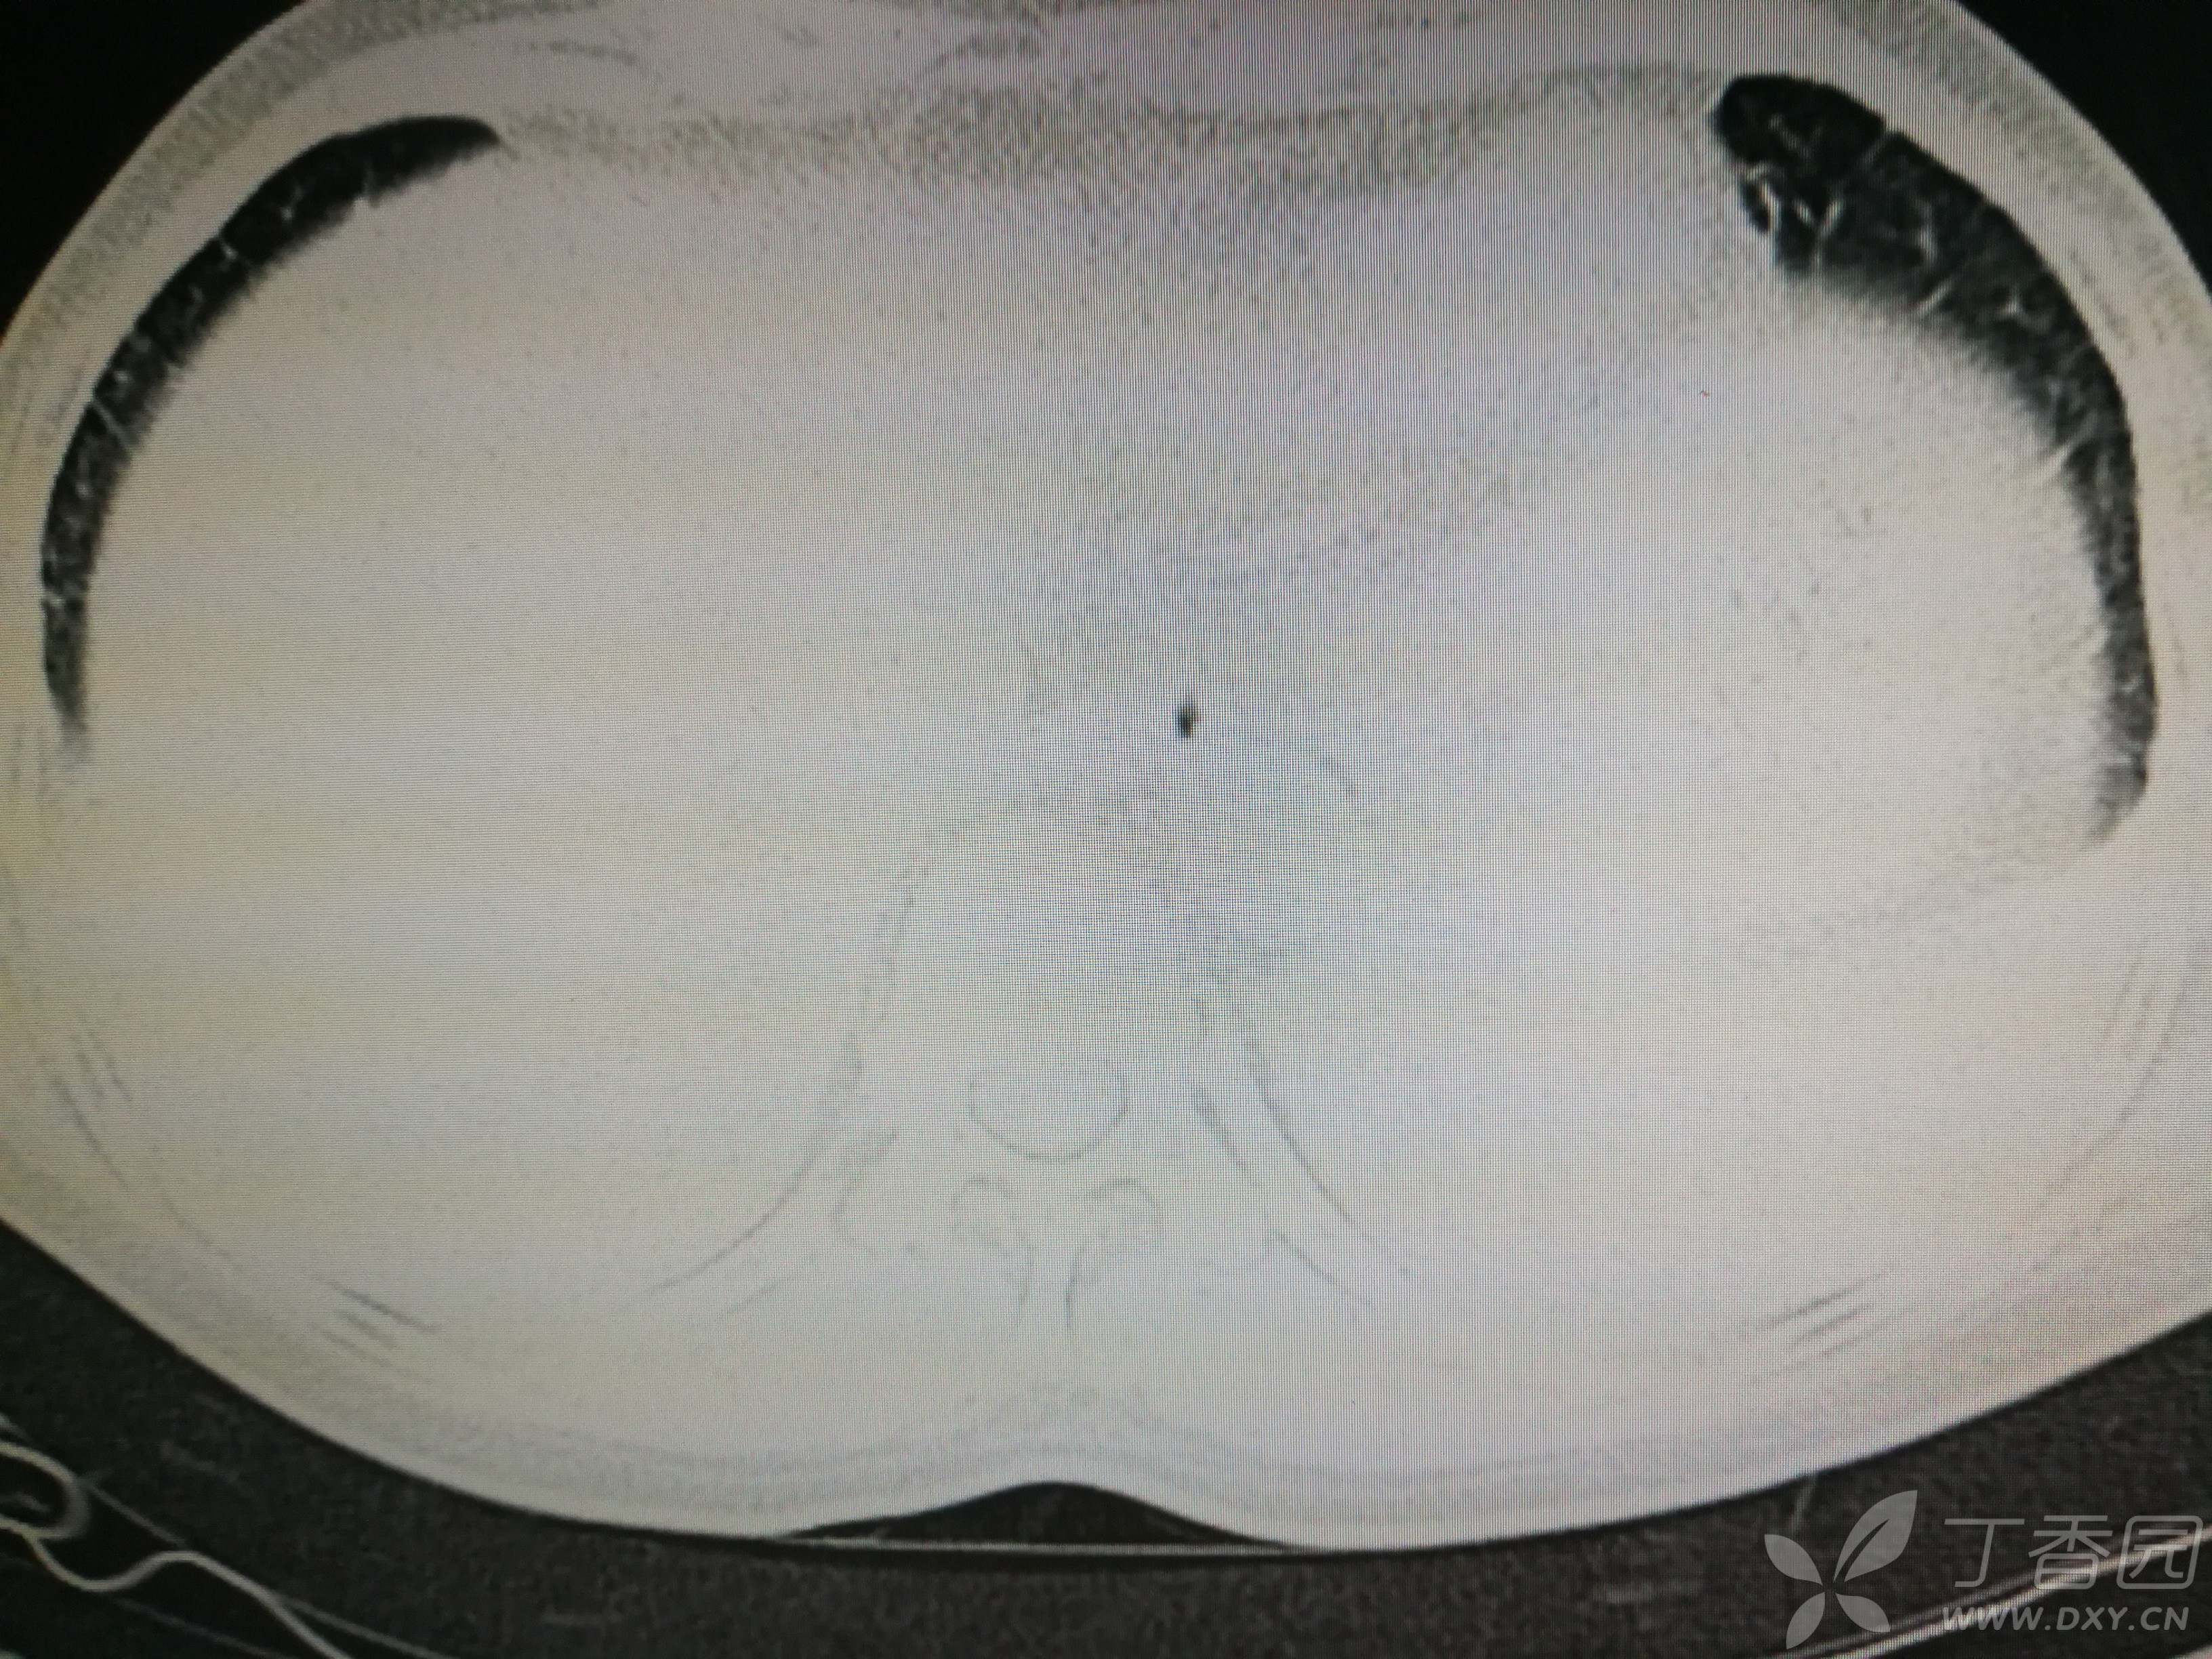

给予低分子肝素钙针抗凝、七叶皂苷钠针消肿及骨牵引固定等等治疗。入院后第四天行“左侧股骨下段骨折切开复位内固定术”(术前查双下肢彩超:双下肢深静脉血流通畅),手术顺利,术后予预防感染、预防血栓形成等治疗。术后患者无明显发热,生命体征平稳。术后第四天复查血常规:白细胞13.4×109/L,血红蛋白84g/L,血小板在正常范围。生化:白蛋白35.7g/L,余无明显异常。当天,患者开始出现轻度胸闷气急,可耐受。术后第五天患者胸闷气急加重,无胸痛,无背痛,无咯血,无意识障碍,无头晕头痛,无恶心呕吐等,急查凝血功能:纤维蛋白原降解产物12mg/L,D二聚体4000ug/L,余无明显异常。查动脉血气分析:pH7.52,氧分压62mmHg,二氧化碳分压30mmHg,碱剩余1.8mmol/L,乳酸1.0mm/L,血红蛋白86g/L。查胸部CT见下(先视频后图片):